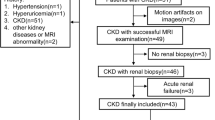

CKD was diagnosed on the basis of persistent proteinuria or chronic decline in estimated glomerular filtration rate (eGFR) (< 60 mL/min/1.73 m2). From a total of 249 CKD patients who underwent magnetic resonance imaging (MRI) between April 2013 and June 2019, those cases with a sufficient number of visits for the treatment and evaluation of CKD (more than three times during a period of at least 1 years) were enrolled (n = 186). We excluded subjects7 who had already received renal replacement therapy such as dialysis or transplantation (n = 4); those under the age of 18 years (n = 3); those diagnosed with primary nephrotic syndrome (n = 13), acute kidney injury (n = 5), or hydronephrosis (n = 1); and those without urinary protein values or blood tests (n = 9), leaving a total of 151 cases. The median and interquartile range of the observation period was 3.75 (2.14, 6.08) years.